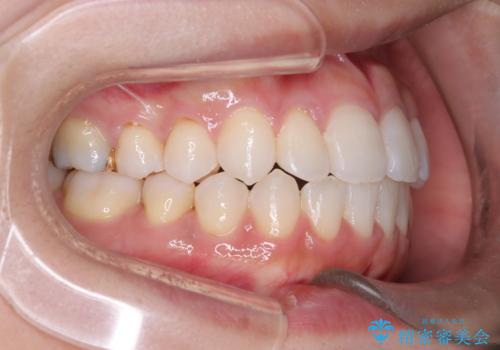

その結果、約10ヵ月という比較的短期間で歯列と咬み合わせが整い、機能面・審美面ともに良好な結果を得ることができました。